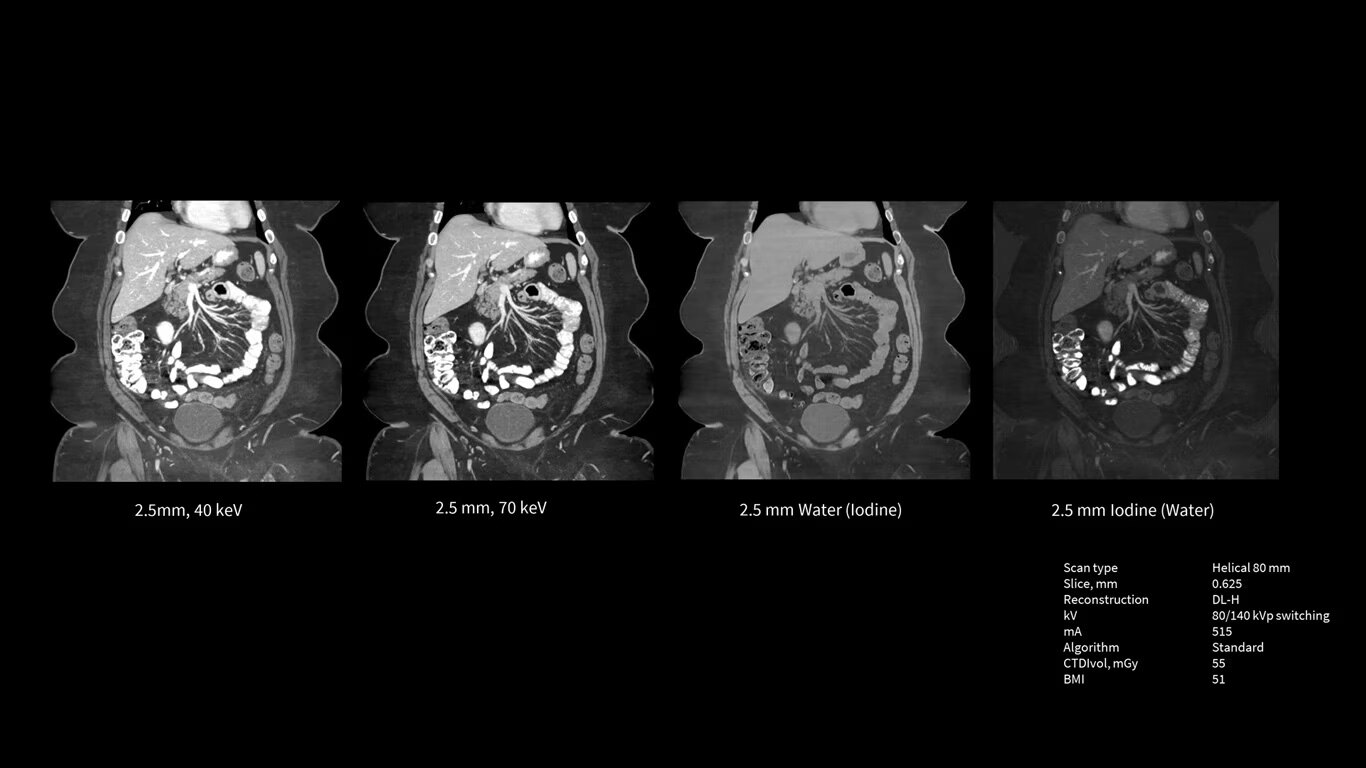

Power like never before

The Revolution Apex platform provides high power output. The ability to upgrade means that siting challenges no longer prevent you from high power output to your department. If your siting power is limited to 150 KVA in the initial installation, you can start with the Power Pro option at maximum 1200 mA, and later on, you can scale up to 1300 mA Power Xtream when you upgrade the powerline.